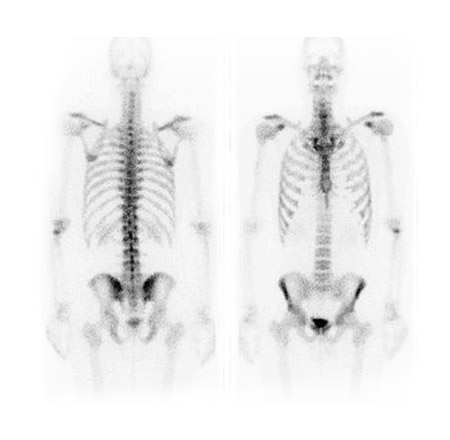

Merivale Medical Imaging offers a full range of outpatient diagnostic imaging services across Ottawa, Kanata, and the Ottawa Valley, from MRI and CT to ultrasound, X-ray, and nuclear medicine.

Explore our full range of outpatient diagnostic imaging services.